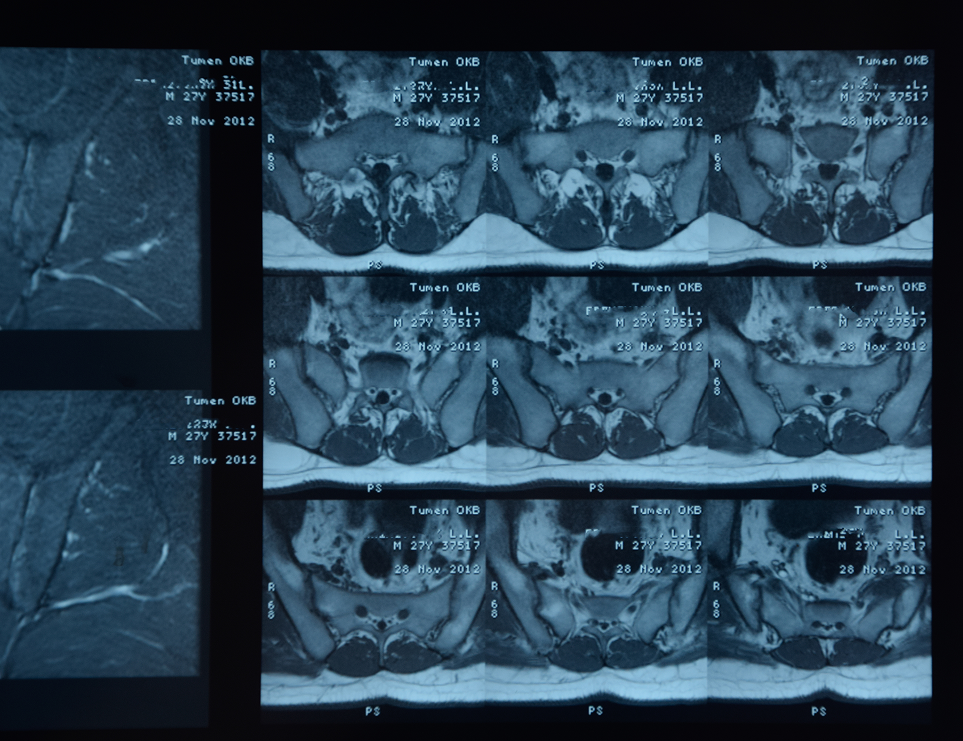

Our cutting-edge segmentation services utilized advanced algorithm platforms to accurately identify and delineate anatomical structures in medical images, which were crucial for effective diagnosis and treatment planning. These technologies enabled us to achieve high levels of accuracy in segmenting anatomical structures and pathological regions within medical images. The applications of medical image segmentation were vast, ranging from Aneurysm detection and organ delineation to the assessment of disease progression. By providing precise segmentation, we empowered healthcare Professionals to make informed decisions regarding diagnosis and treatment planning. We completed many segmentations with accuracy and quality across various parts of the body and different imaging modalities (Such as CT, MRI, DSA, etc.) covering a range of pathologies (Such as Occlusion, Infarct, Dissection, etc.) in multiple types of imaging (CTA, NCCT, MRA, etc.).

- MRI Image Segmentation for neurological disorder analysis, including brain tumors and multiple sclerosis.

- MRI Image Segmentation assists in diagnosing brain disorders like Alzheimer’s and stroke.